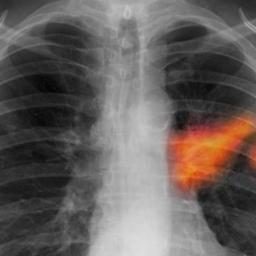

AstraZeneca lung cancer drug given green light in US

FDA approval of Tagrisso offers major boost for British company, seeking to release six new cancer medicines by 2020A new lung cancer pill from AstraZeneca has been approved by US regulators, in a major boost for the British drugmaker.AZD9291, which will be sold as Tagrisso, is for advanced non-small-cell lung cancer, the most common form of lung cancer. Tagrisso targets a genetic mutation, known as T790M, that helps tumours evade current lung cancer pills. The drug will be made available to patients in the US as soon as possible and its price will be “comparable to other oral cancer therapies,” a spokeswoman said. AstraZeneca will reveal the price early next week. Continue reading...